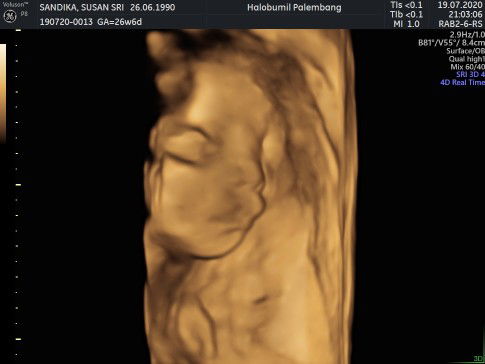

sedang mengandung